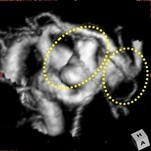

脳動脈瘤・くも膜下出血

くも膜下出血の原因となる脳動脈瘤の治療を、直達手術、血管内治療を用いて行います。

近年では、動脈瘤ができた部位の血管内に、

フローダイバーターとよばれる血流改変ステントを

留置して、動脈瘤の血栓化を促す治療も行います。

当院でも施行可能です。

フローダイバーター留置術(血管内治療)

治療前(血管造影画像) 治療後(血管造影画像)

複雑な形状の動脈瘤を認め、フローダイバーターを留置し、動脈瘤の消失を確認しています。